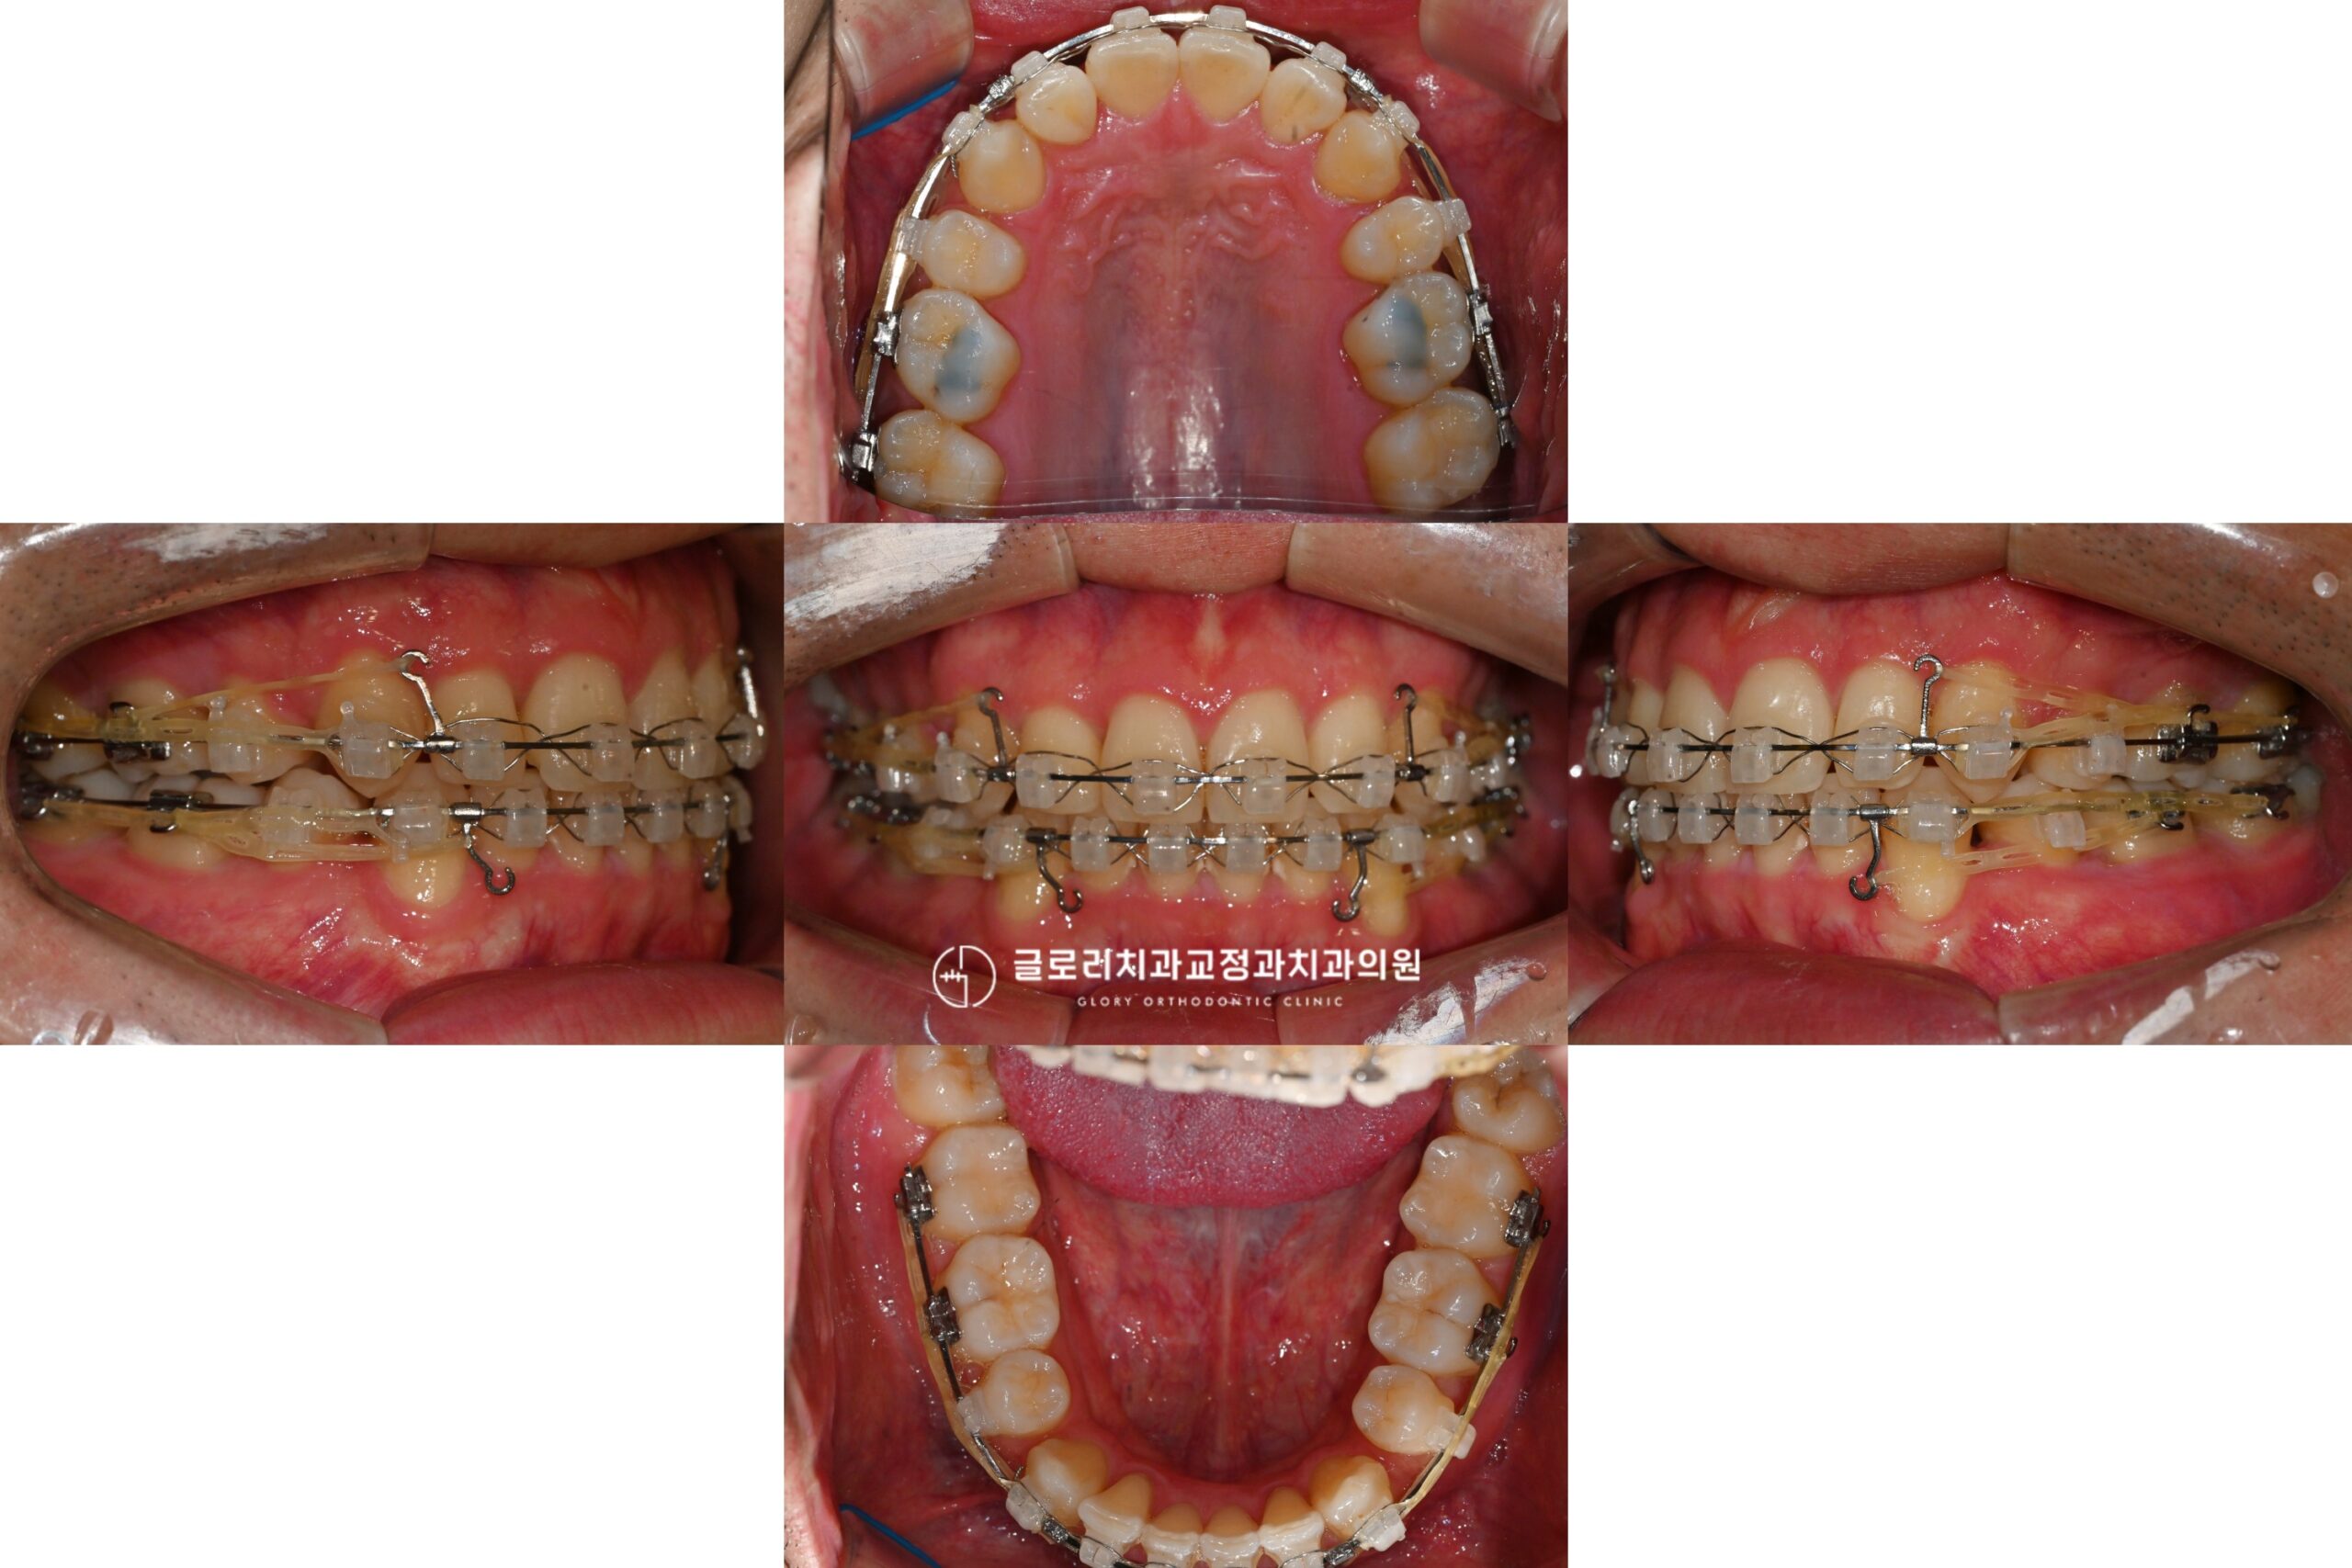

망우역 교정치과 에서 발치교정에 많이 활용하는 장치 중 하나가 클라리티 울트라(Clarity Ultra)입니다.

클라리티 울트라는 미국의 글로벌 기업 3M에서 개발한 자가결찰 세라믹 브라켓입니다.

클라리티 울트라는 이러한 자가결찰 방식에 심미성까지 더한 장치입니다.

클라리티 울트라는 세라믹 재질로 제작되어 치아 색상과 유사합니다.

실제로 장치를 부착한 모습을 보면 브라켓이 치아와 자연스럽게 어우러져 멀리서 보면 잘 눈에 띄지 않습니다.

- 치료기간: 23.10.28 ~ 25.11.28